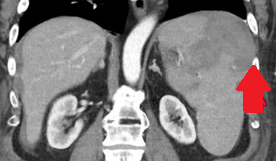

Presence of multiple metastases in the right lobe of the liver, 3 years after left hemicolectomy (Courtesy Dr. V. Penopoulos)